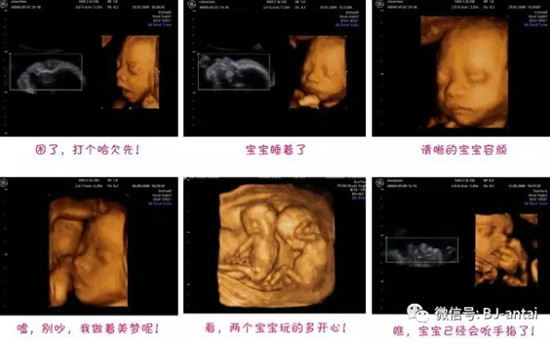

四维视频观赏: